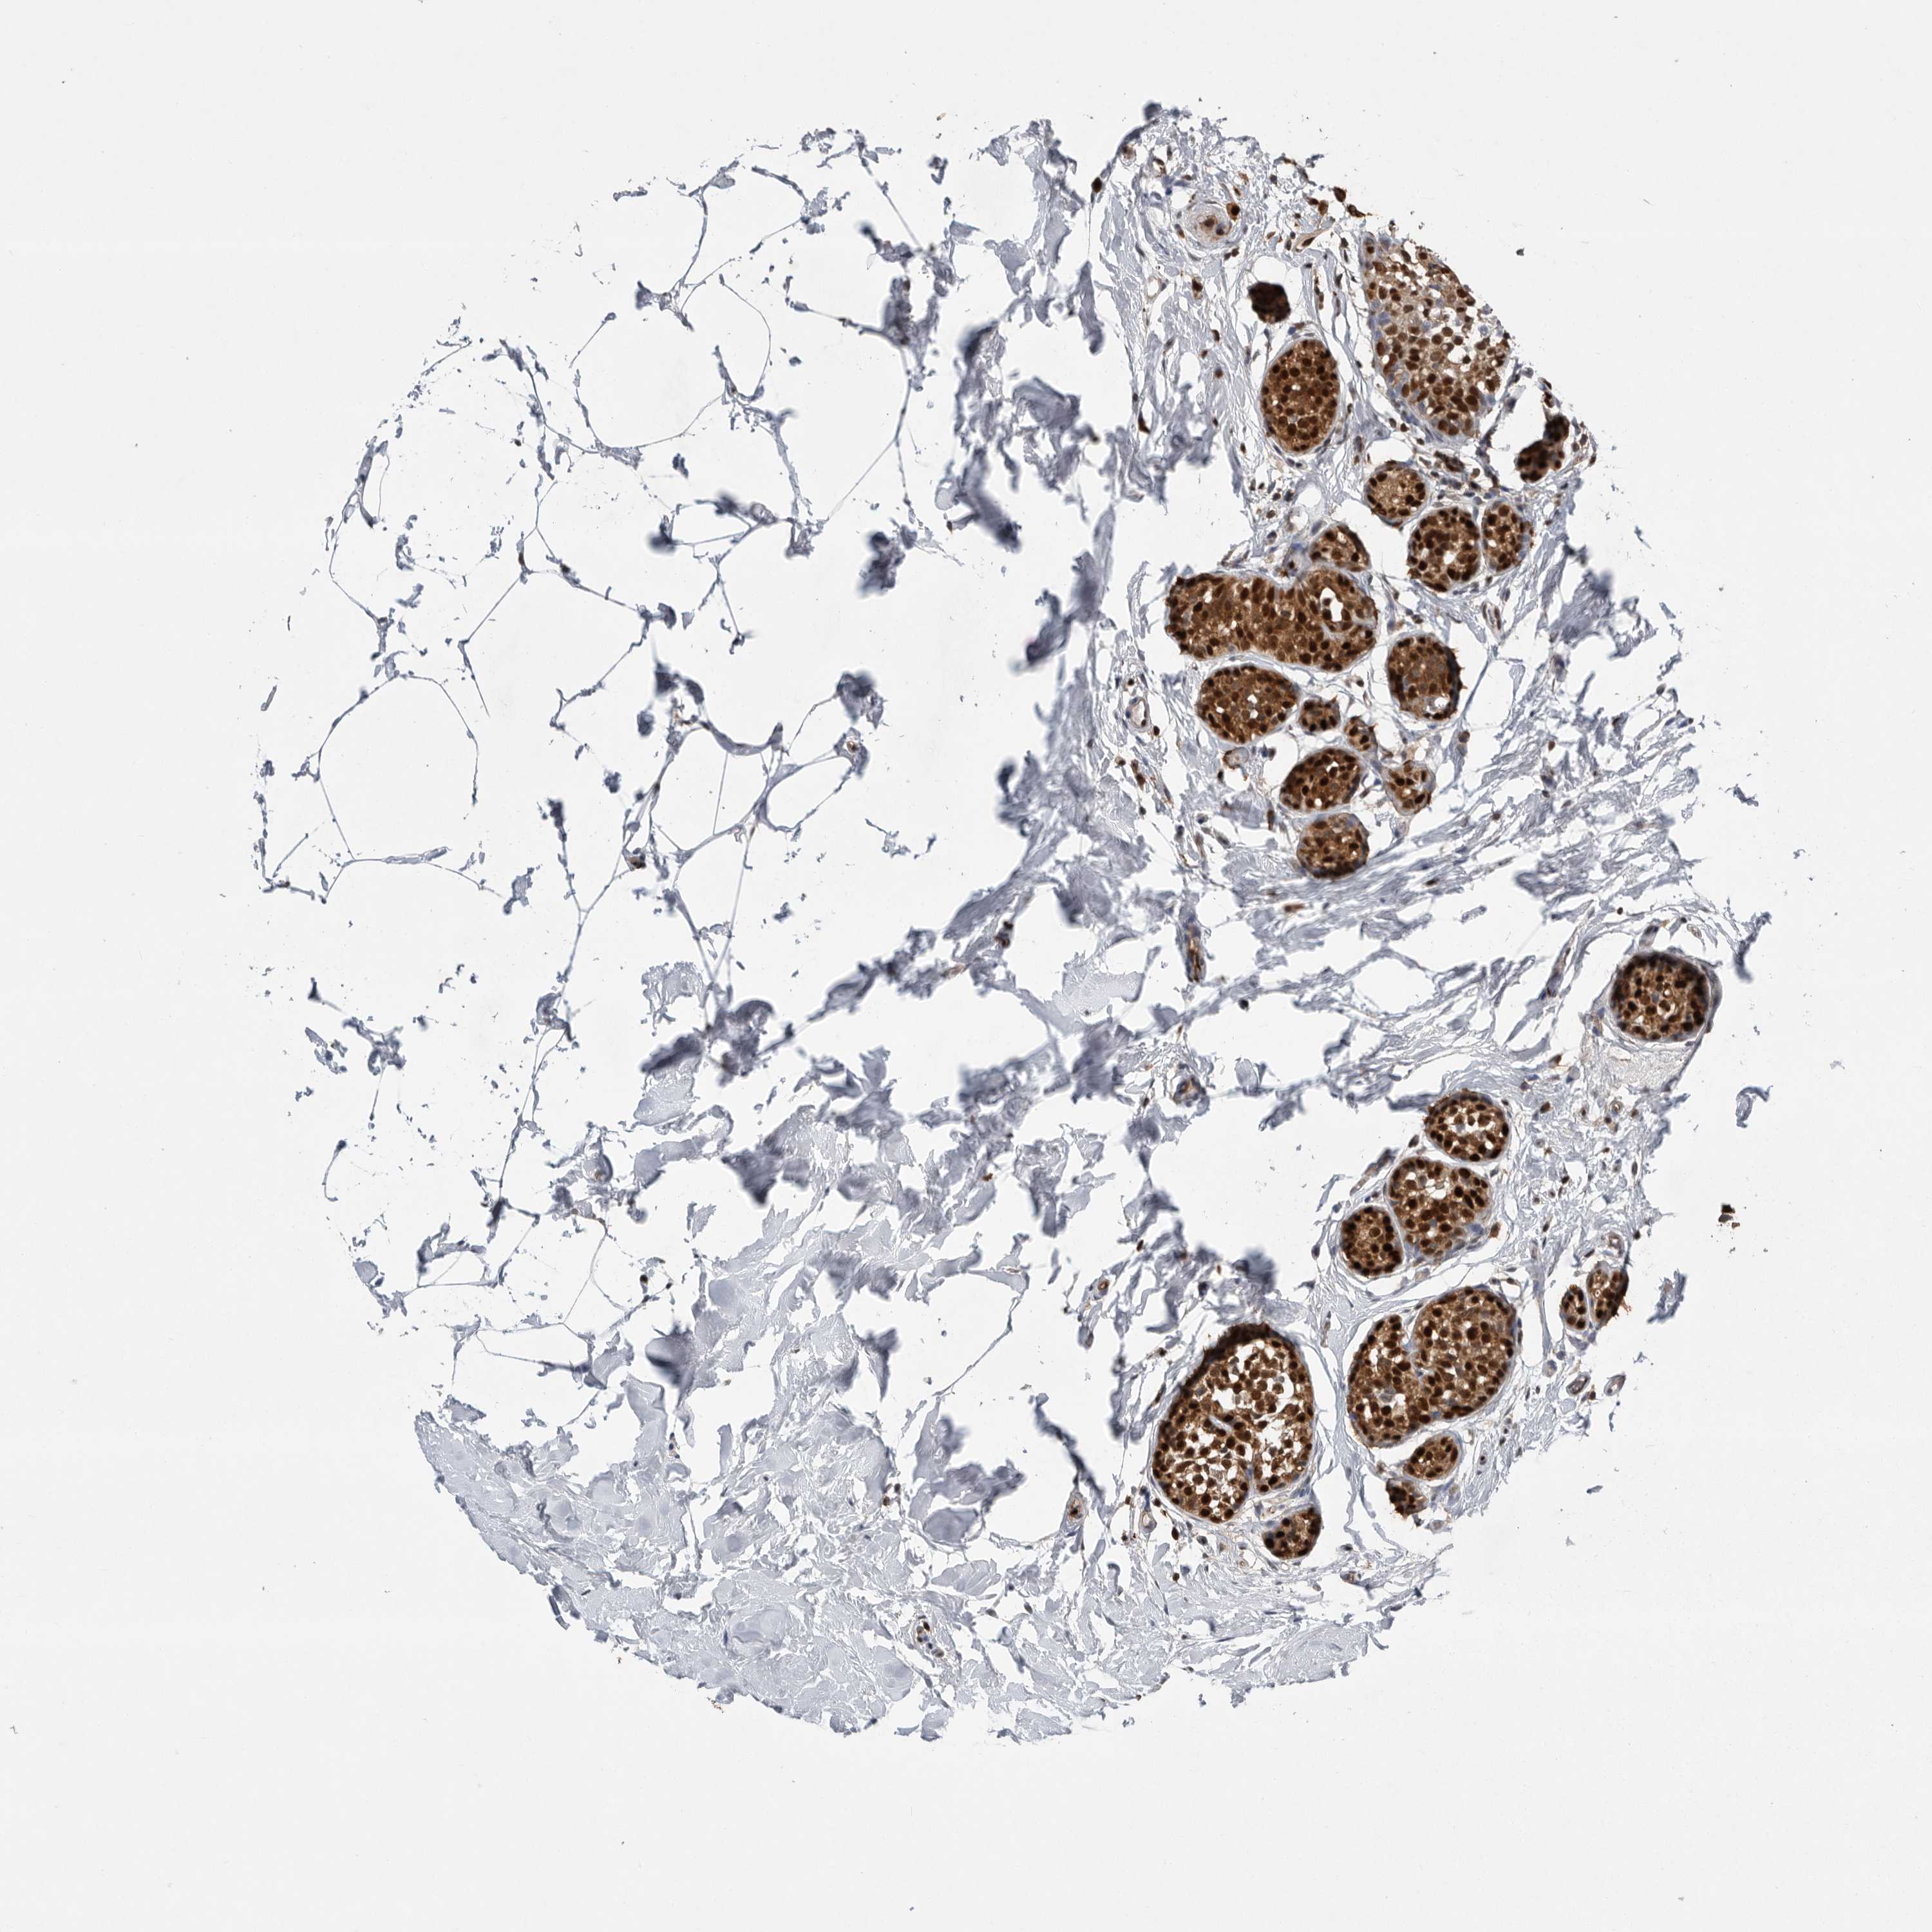

CANCER BREAST CANCER Show tissue menu

BRCA TCGA BRCA VALIDATION PROTEIN EXPRESSION

Breast cancer

Human cancer